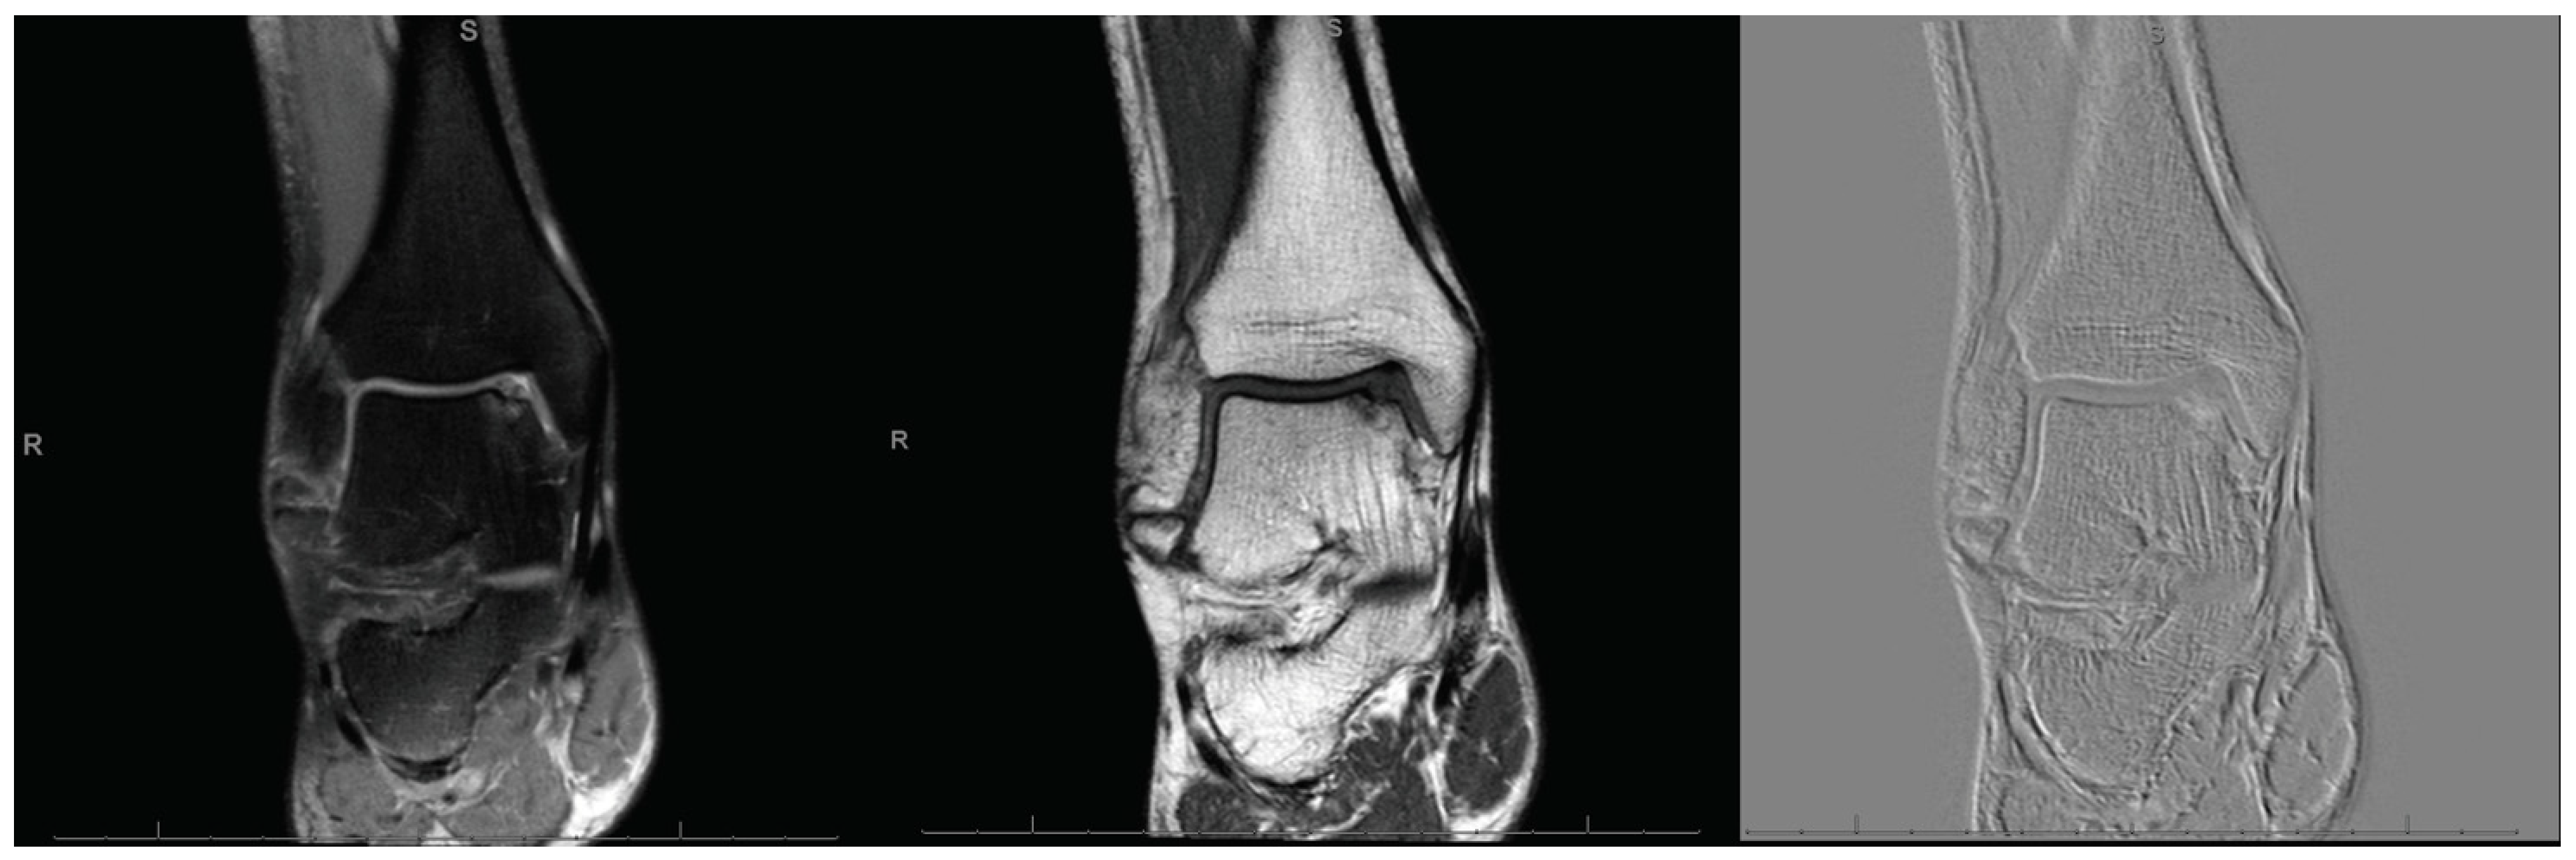

The present study was performed according to Strengthening the Reporting of Observational Studies in Epidemiology: the STROBE Statement [30]. In our setting, for patients with defect sized 2 to 3 cm2, both AMIC or isolated MFx were routinely performed. From 2012, patients undergoing primary isolated AMIC or MFx for focal unipolar borderline sized chondral defects of the talar shoulder (Figure 1), were recruited and followed-up prospectively. The inclusion criteria were: (1) symptomatic chondral defect of the talar shoulder, (2) single focal defect sized 2 to 3 cm2, (3) MRI evidence, (4) patients able to understand the nature of the treatment and the study. The exclusion criteria were: (1) kissing lesions, (2) bilateral lesions, (3) multifocal lesions, (4) previous ankle surgeries, (5) any bone disease, (6) any skeletal malformation, (7) any other relevant pathology that could have influenced the study. Suitable patients were informed about the pros and cons of both techniques, and were left free to decide their own procedure. The present study was approved and registered by the ethic committee of the RWTH University of Aachen (project ID EK 438-20), and conducted according to the principles expressed in the Declaration of Helsinki. All patients were able to understand the nature of their treatment and provided written consent to use their clinical and imaging data for research purposes.

Figure 1.

MRI evidencing a focal defect of the medial talar shoulder.